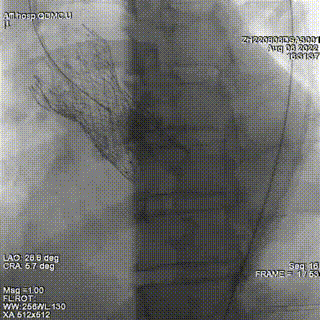

通过交换导丝置换鞘管,置入入第一枚封堵器6mm ADOII。

确定第一枚封堵器置入位置理想,但造影仍提示瓣周反流。